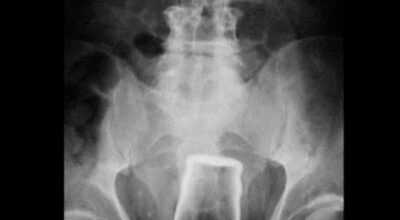

Esta recopilación de imágenes recoge alguna de las situaciones más estrambóticas que se han podido dar en una sala de rayos X. Todas ellas tienen algo en común: Son objetos extraños para el cuerpo humano que, de alguna manera han encontrado una vía de entrada, pero se han perdido a la hora de encontrar la de salida.

Muñecas de juguete descabezadas, botellas, armas, frascos, botes de plástico, teléfonos y hasta una cinta de casete pueden encontrarse en esa suerte de “punto limpio” al que ha quedado reducido el interior de los afectados.